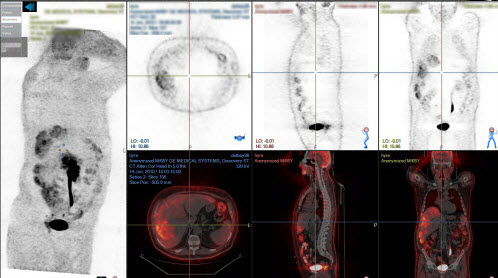

Sample layouts and views

The following examples show common ways to arrange images using study layouts and views. Available views depend on your NilRead implementation.

Multiple viewports

When a view is applied to a screen, the screen may be divided into multiple viewports. In the following example, the MPR 3D view has been applied to the first screen, dividing the screen into four viewports. Note that a different view (or the same view) could also be applied to the second screen.

PET-C fusion view